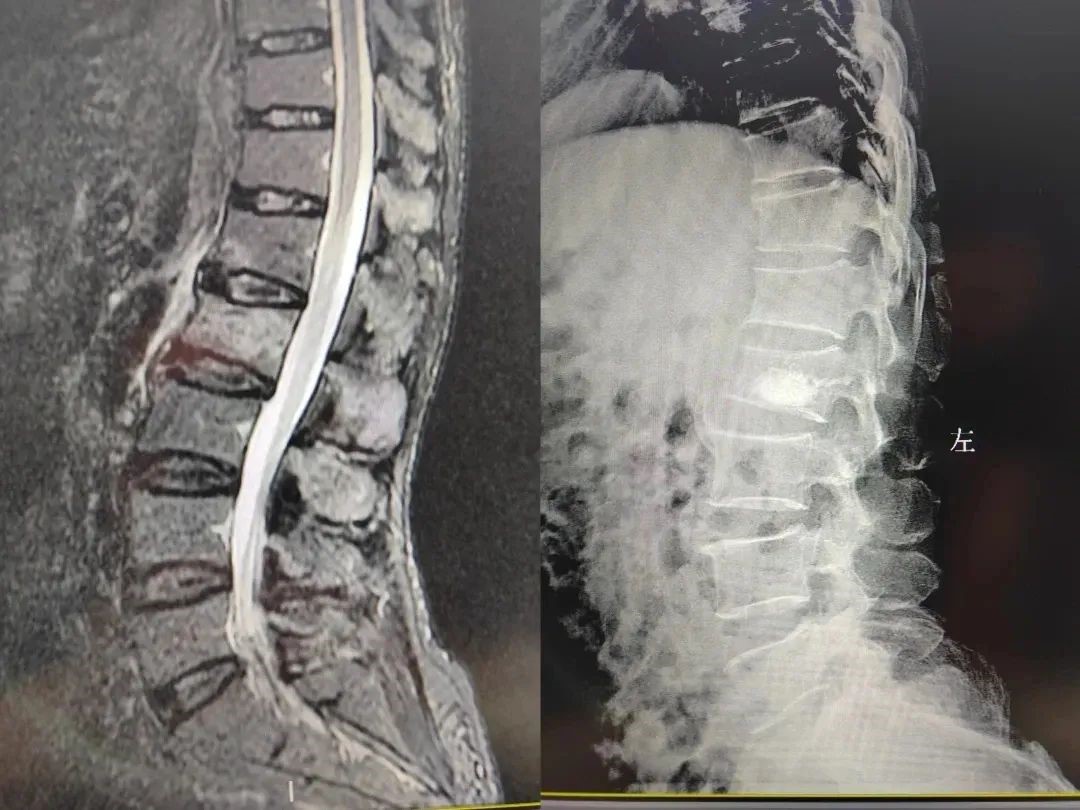

病例一

62岁男性患者,因摔伤致腰背部疼痛,伴屈伸活动受限,床上翻身、久站后疼痛加重明显,特来我院就诊。骨二科团队经过辅助检查诊断为腰2椎体压缩性骨折,需要尽快进行手术。

患者入院后立即为其完善各项术前准备工作并制定详细的诊疗方案,向家属详细讲解手术过程及预见性采取的措施,解除患者及其家属心中的不安及疑虑。在手麻科的保驾护航下,骨二科团队在局麻下行经皮穿刺腰2椎体球囊扩张成形术。

凭借娴熟、精准的手术技巧及丰富的临床经验,骨二科团队安全、快速地完成了手术,患者术后病情稳定,恢复良好,患者及家属对医院骨二科团队高超的手术技术和辛劳付出表示了肯定和感激,对手术治疗方法及术后护理都非常满意。